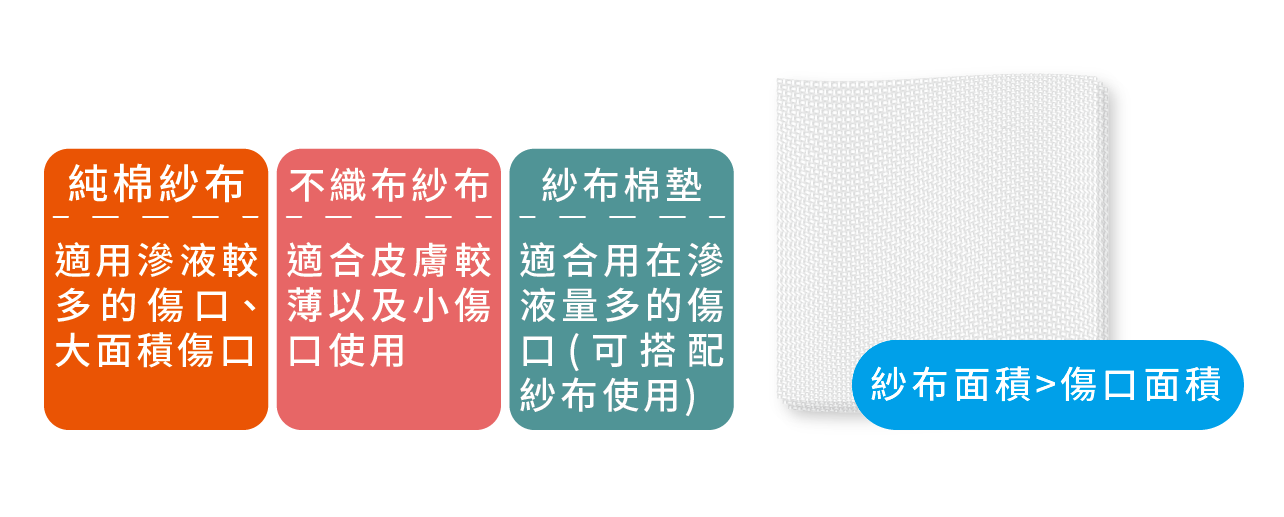

用對人工皮,傷口神救援!

您家裡是否有個活潑的孩子,常常摔跤跌傷、造成傷口?此時,很多父母會想到「人工皮」。所謂的人工皮是一種親水性敷料,適當使用人工皮覆蓋在傷口上,能維持傷口的濕潤並吸收傷口的分泌物,有助傷口修復。但是,食品藥物管理署(下簡稱食藥署)提醒,如果沒有選對、貼對人工皮,反而容易造成傷口感染。

人工皮貼多久?什麼時候該換?看這個來判定

受了傷不想留下疤痕,大部分的人都會選擇貼「人工皮」,促進傷口癒合。但常聽到人說,「人工皮」不用每天更換、貼越久越好?食藥署表示,一般而言,人工皮可黏貼2~3天,視傷口滲液狀況再進行更換,建議不可使用超過7天。